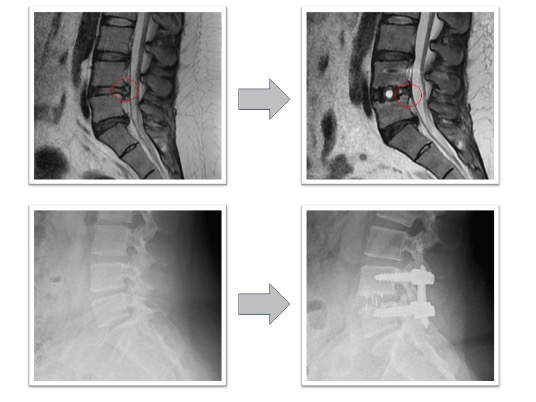

腰椎すべり症+椎間板ヘルニア(図2)

下肢痛で来院し歩行困難のため手術となりました。術前認められていたL3/4の椎間板ヘルニアがOLIFによる固定術後消失(赤丸)、またL4/5に認められていた変性すべり症による椎体のずれ、不安定性も術後は元の脊椎の並びに矯正された状態で固定されています(黄丸)。術後は症状消失し、元通り歩行可能となりました。

図2

変性側弯を伴う多椎間の椎間板ヘルニア、脊柱管狭窄症(図3,4)

下肢痛、歩行障害、腰痛で来院、手術となりました。術前後のレントゲンで3椎間のOLIFによって術後側弯症が改善され、脊椎の並び(アライメント)が矯正されています(図3)。また、術前後のMRIでは施術した部位の椎間板ヘルニアおよび脊柱管狭窄がOLIFの間接除圧効果によって改善し、神経への圧迫が解除されています(図4)。術後は歩行可能、下肢痛腰痛も改善、また結果として数センチ身長が回復しています。

図3

図4